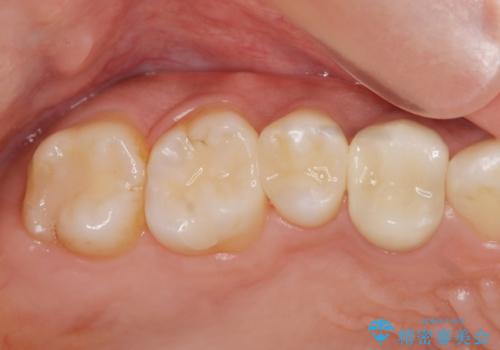

- 27万円(セラミックインレー×2 仮歯・ファイバーコア・ジルコニアクラウン)費用は治療当時の料金となります

虫歯治療は小さい場合にはセラミックインレー、大きな場合や痛みが生じている場合は根管治療ののちクラウンによる機能回復が必要となることが多いです。